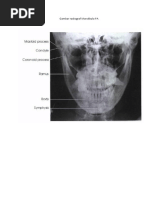

ANATOMI